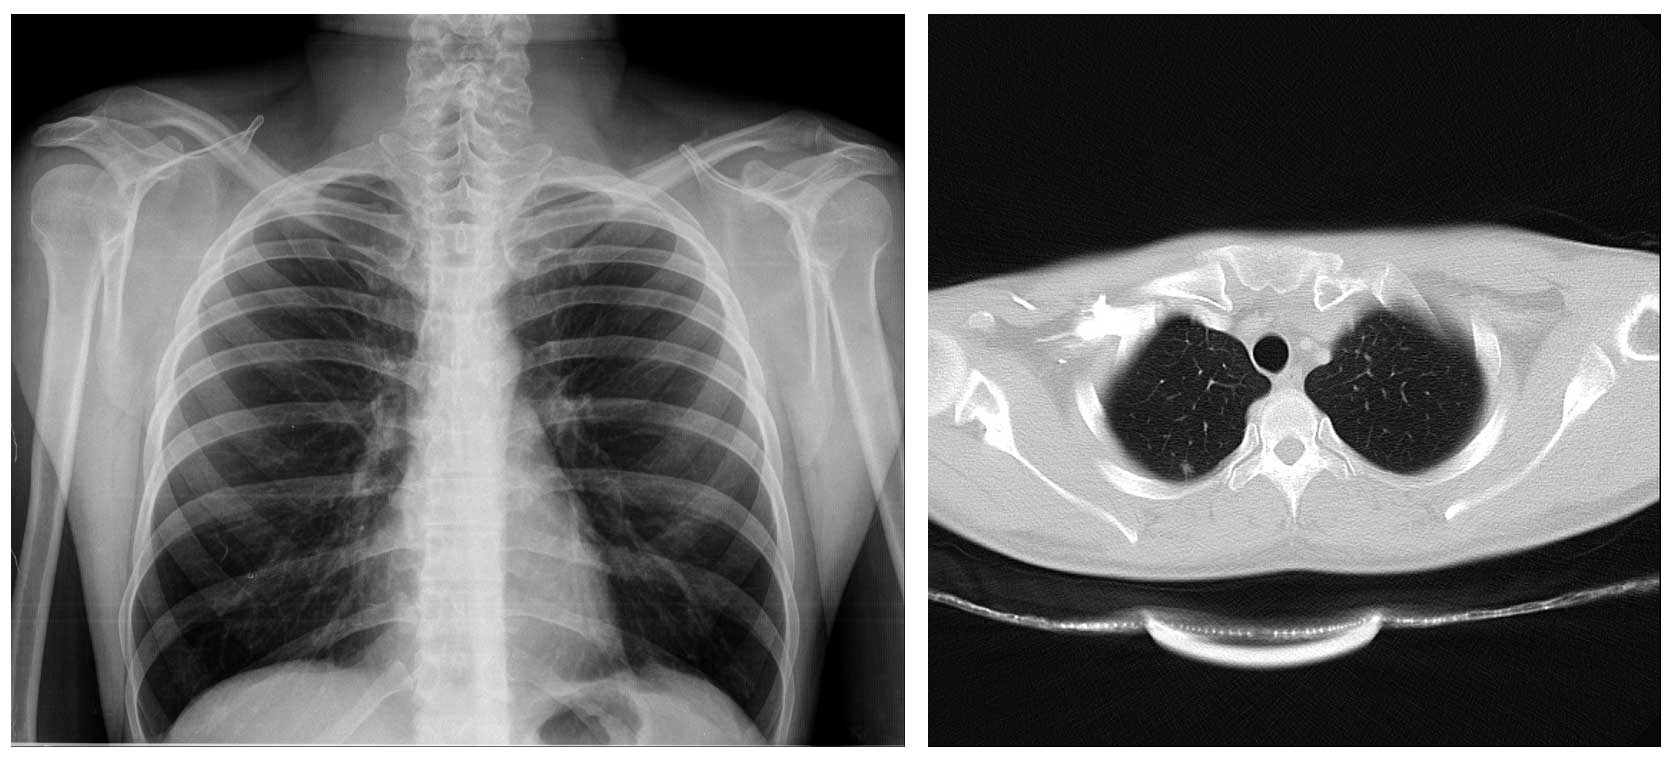

Ameliyat Öncesi: Röntgende özellik yok iken tomografide kemik harabiyeti görülmekte.